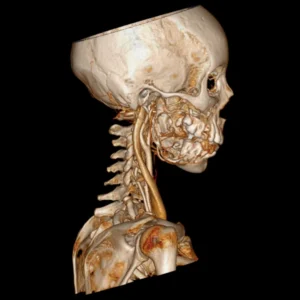

Hiperplasias o hipoplasias condilares

Es una enfermedad rara que se considera un crecimiento patológico y progresivo de uno o ambos cóndilos mandibulares, cuanto más grave es la patología, mayor asimetría y maloclusión desarrolla, que no solo afecta al desarrollo, masticación, deglución, habla, etc. si no que además esta particular entidad afecta altamente al individuo en un nivel psicosocial.

Cirugía ortognática (asimetrías faciales)

Corrección quirúrgica de deformidades óseas en mandíbula y maxilares para mejorar estética, mordida y respiración.

La cirugía ortognática, del griego orthos, «recto» y gnathos, «mandíbula», es una intervención quirúrgica que se encarga de corregir las deformidades dento-craneo-maxilofaciales mediante movimientos óseos maxilares y mandibulares, para lograr el equilibrio perfecto entre todas las características faciales del paciente.

Este tipo de alteraciones faciales aparecen en la fase de crecimiento de los pacientes, se estabilizan al final de la misma, y pueden causar problemas como apnea del sueño, trastornos de la ATM, problemas de maloclusión o falta de armonía esquelética, entre otros.